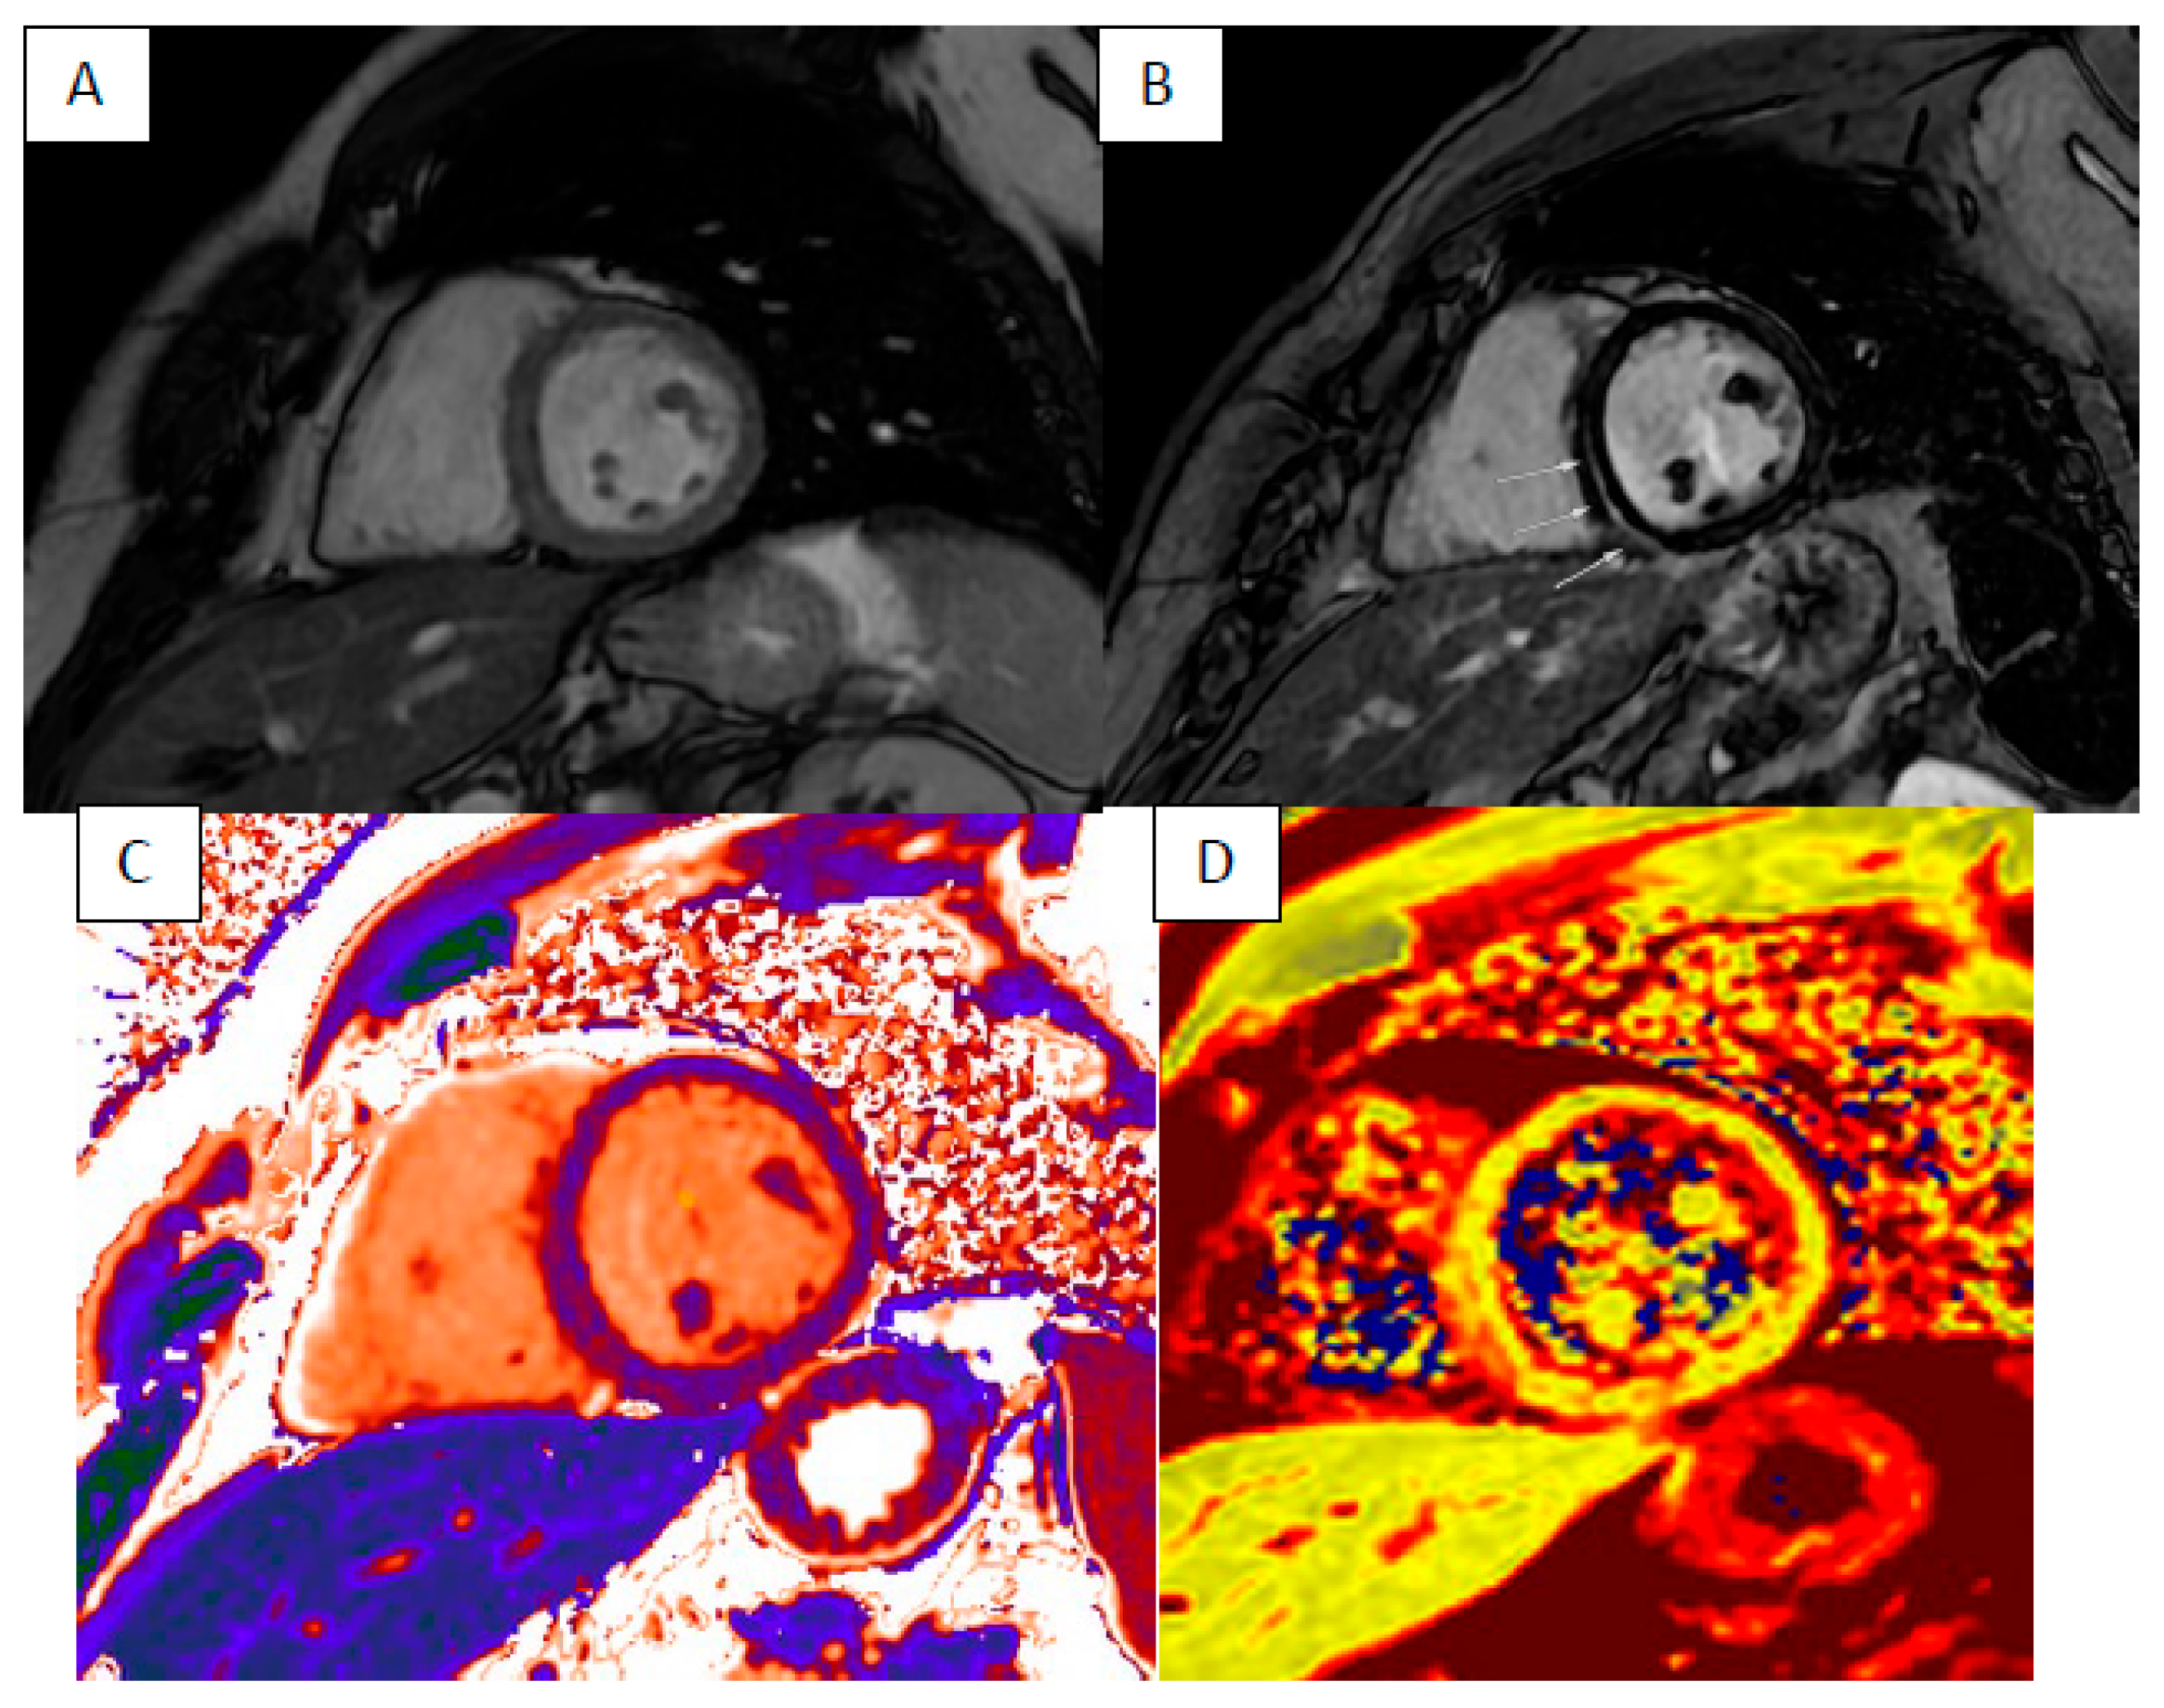

3. Cardiac Sarcoidosis